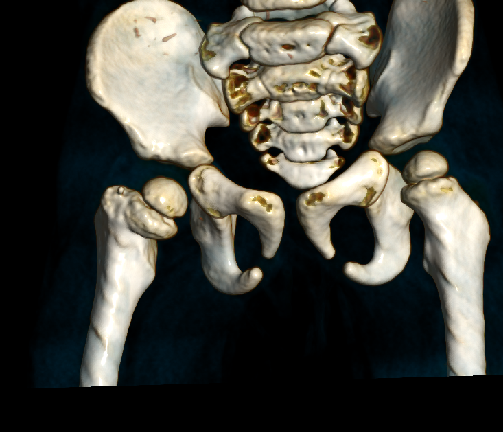

影像资料:

DR提示:右侧股骨颈骨折,断端错位,右股骨干上提,颈干角缩小,右股骨干未见明显异常,双侧髋关节关系未见明显异常,余无特殊。

诊 断:

股骨颈骨折,骨折端移位。

针对此病例诊断及治疗方案,周乙雄教授指导如下:

此病例诊断为股骨颈骨折不够准确,一定要仔细查阅患者X光片。周主任认为此病例诊断为股骨头骨骺分离更确切,伴有半脱位。

此病例特点是患者年龄小,可塑性强,若采用保守治疗,可用手法复位, 双下肢皮牵引,臀部离床5-10公分。如果采用手术切开复位内固定,一定要考虑手术可能会引起肢体发育长短、股骨头畸形及坏死等合并症。因此治疗方案宜根据当地医疗条件、家属意愿等综合评估。